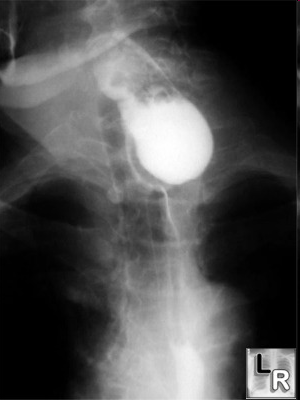

- Kontrastlı Rh-qrafiya - diaqnozu dəqiqləşdirən müayinədir.

- Rentgenoqrafik divertikul görünməsi

- Kontrastlı Rh-qrafiya - dəqiqləşdirici müayinə üsuludur.

Kontrast məhlulunn divertikul nahiyəsində toplanması

Kontrast məhlulun divertikul nahiyəsində toplanması